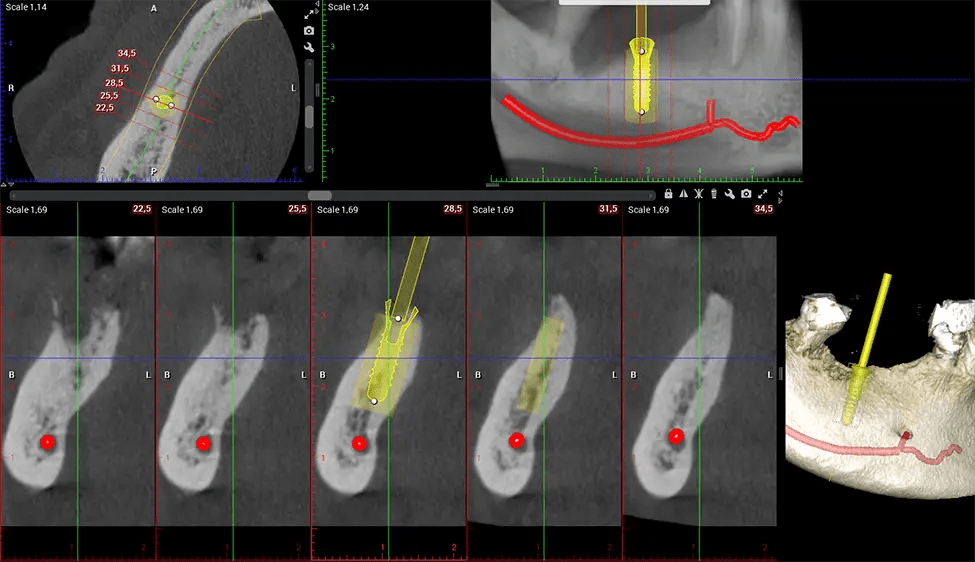

Cone Beam Computed Tomography (CBCT) is an advanced imaging technique used in dentistry and maxillofacial surgery to obtain detailed 3D images of the oral and maxillofacial structures. At Dr G Dental Studio, our CBCT scanners utilize a cone-shaped X-ray beam and a specialized detector to capture images from different angles. A computer then combines these images to create a 3D representation of the patient’s oral anatomy.

After the scanning process, the captured X-ray images are processed by the CBCT software, which applies algorithms to reconstruct a detailed 3D image of the scanned area. The software compiles these individual X-ray images and creates a digital 3D representation of the patient’s anatomy. The reconstructed 3D CBCT image can be viewed and analyzed by the dentist or radiologist. This image can be manipulated, rotated, and zoomed in or out to examine specific structures and evaluate the patient’s condition.